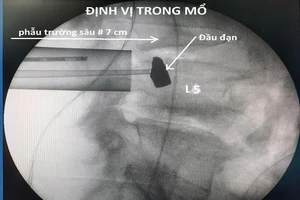

Lấy thành công đầu đạn 51 năm nằm trong cơ thể